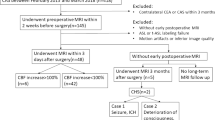

According to the distribution of HI among included patients (Fig. 2b), the last 17 patients with significantly higher HIs (log HI > 4.5) were grouped as cerebral hyperperfusion. The overview of processing steps with two representative cases is shown in Fig. 2.

Overview of processing steps with two representative cases. a Preoperative and postoperative cerebral blood flow (CBF) maps were registered to non-labeled arterial spin labeling (ASL) and 3D T1 space and then divided to generate CBF ratio maps. CBF ratio maps were normalized and masked with a cerebral flow territory template to acquire hyperperfusion volume in the ipsilateral middle cerebral artery territory. b The distribution of hyperperfusion indexes (HI) among 86 included patients. Case 1 was identified as non-hyperperfusion, case 2 was identified as hyperperfusion. Red dots indicate patients with cerebral hyperperfusion syndrome. A cross indicates HI is 0

From May 2015 to July 2021, 111 patients were initially included in the study. Among the 111 patients, 7 had MRI contraindications, 5 did not finish two MRI scans, 5 were observed with intracranial artery stenosis or occlusion on preoperative CTA, 2 had massive ischemic stroke, 1 had postoperative treatment with mannitol for 7 days before MRI, and 5 had artifacts on the ASL images. A final 86 patients were enrolled for analysis (Fig. 3). The mean age of the included patients was 65.3 ± 7.1 years, and 75.6% were male. Thirty-two patients (37.2%) had symptomatic carotid stenosis. CEA was successfully performed in all patients. Cerebral hyperperfusion was present in 17 (19.8%) patients. Hyperperfusion occurred most frequently in the distal flow territory of the middle cerebral artery (M4–6) and watershed area (Figure S1). The characteristics of the study population are shown in Table 1.